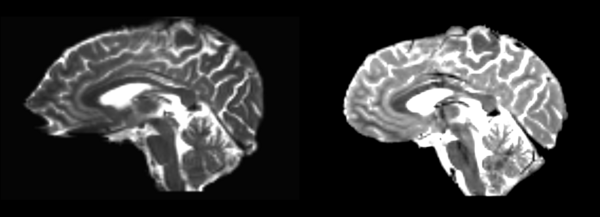

Affine

- 53-t2 -> 31-t1 = aff1

- aff1 -> 53-t2 = aff2

The image shows these side by side. The are nearly the same except for the loss of fine detail.